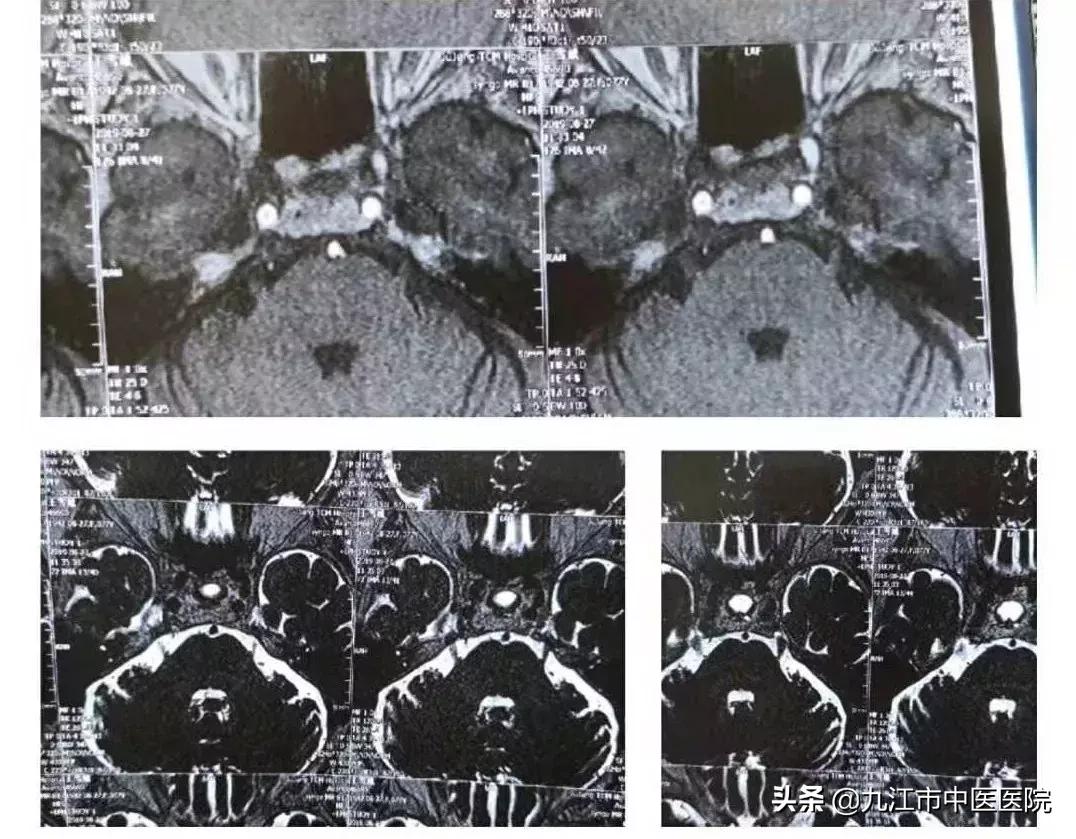

据宗志涛介绍,该患者为一名80岁的高龄女性,右侧面部疼痛不适已有12余年之久。期间通过针灸、射频等治疗未见疼痛改善,后因不适感加重,无法触碰面部,寝食难安,只能靠止痛药勉强缓解。在朋友介绍下,来到脑病科就诊。宗志涛及团队接诊后,详细询问了该患者病史并详细查体,结合头部磁共振检查,右侧三叉神经旁可见血管与之毗邻,确诊患者为典型的三叉神经痛。